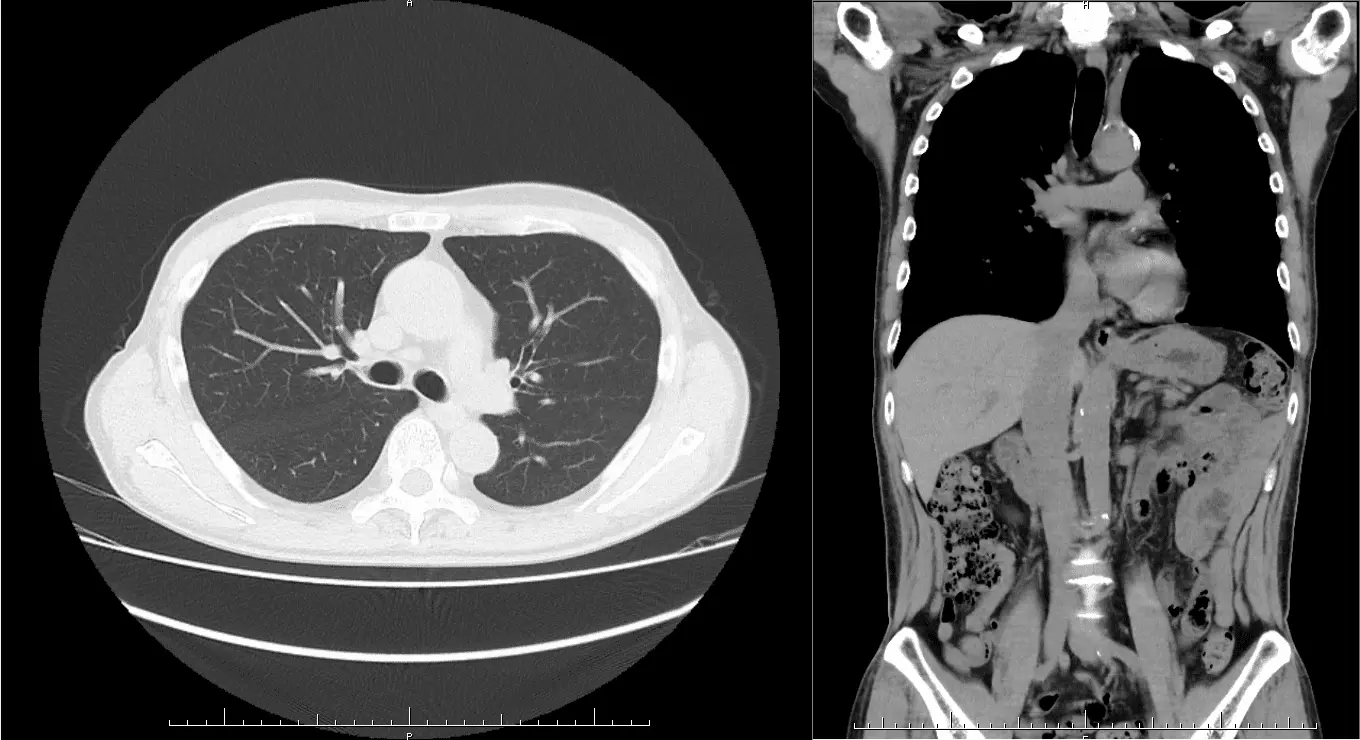

Seeds Clinic新宿三丁目では、CT装置を使った超低被ばく肺がん検診を実施しています。一般的な肺がん検診で行なわれる胸部X線検査(胸部レントゲン)では、骨との重なりで病気がわかりにくかったり、影が薄く小さいと見えにくいことがあります。CT検査ではこのような影が薄かったり、小さいタイプのがんでも見つけることができます。

レントゲン画像では影はほとんど見えませんが、CTでははっきりと映っているのがわかります。また、レントゲンでは心臓や横隔膜に隠れている場所もCTではしっかり見ることができます。胸部X線検査ではX線を使っての撮影となりますので、被ばくがあります。人間ドックなどで胸部X線撮影を正面と側面の2方向撮影をすると、約0.15mSv(シーベルト)の被ばくになります。日本での宇宙や大地、食物や空気中に存在する天然の放射性物質からの自然放射線による被ばくは1年間で約2.1mSvです。低被ばくでありながら、精度の高い検査が可能です。

当クリニックの胸腹部CT検査では、肺や腹部臓器(肝臓、膵臓、胆のう、腎臓など)を高精度にチェックできます。この検査により、早期の肺疾患や消化器系の病気をいち早く発見し、早期治療のきっかけを掴むことが可能です。